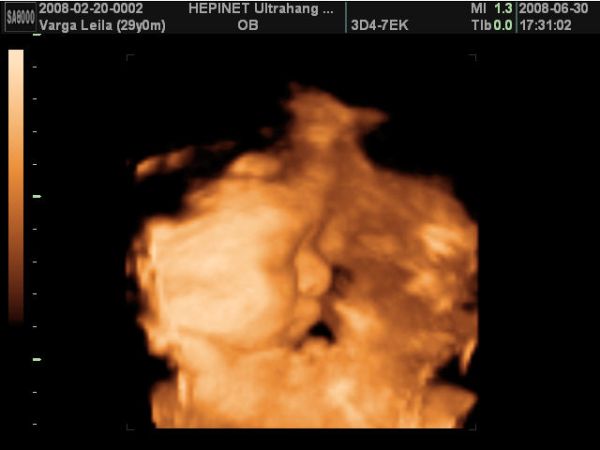

Azért,ha nem baj, mutatok két képet a kisfiamról a pocimban. A képek múlt héten készültek 4D-n:

Kép Csabi

Kép Csabi2